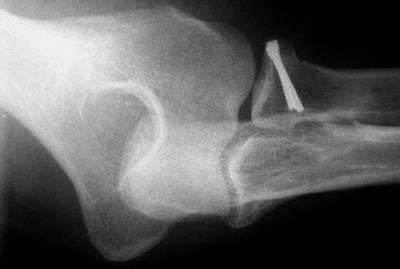

Рентгенография

Рентгенография обеспечивает визуализацию плотных анатомических структур, которыми являются ваши кости. Это основной метод диагностики переломов в области локтевого сустава.

Рентгенограмма локтевого сустава в боковой проекции, на которой представлен перелом локтевого отростка со смещением

Для определения перелома выполняется рентгенография локтевого сустава в двух проекциях. Этого исследования достаточно в большинстве случаев. Для более детального исследования характера перелома выполняют компьютерную томографию (КТ). С её помощью можно определить насколько разрушен отросток и определиться с тактикой лечения. Выполнять ли операцию и с использованием какой металлоконструкции. Все эти ньюансы очень важны для лучшей фиксации и наилучшего исхода лечения.